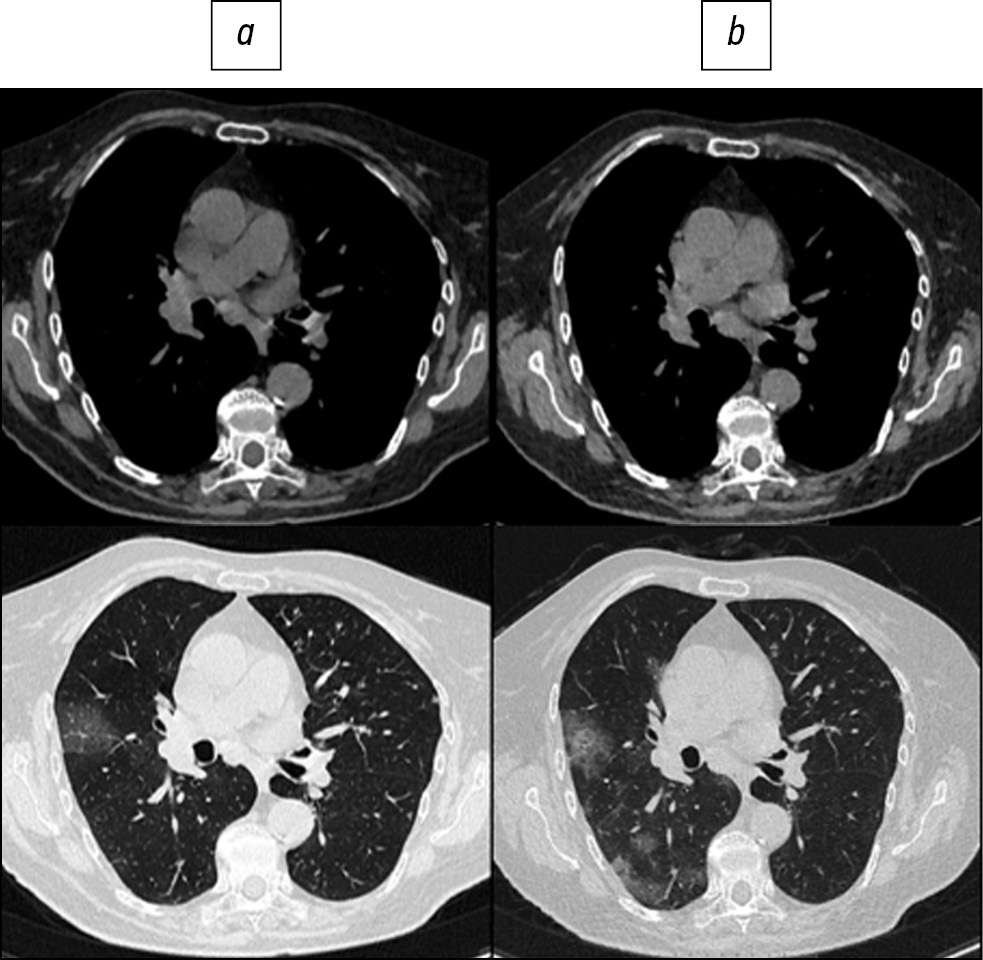

Fig. 2. Patient, 72 years old: standard computed tomography at admission was performed with radiation exposure of 2.1 mSv (a), low-dose computed tomography - 0.87 mSv (b).

Here are illustrative examples of clinical cases (Figs. 1–6), demonstrating the similarity of diagnostic value of two aforementioned research methods. Columns on the left (a) show images of a standard CT scan performed upon admission of the patient to the hospital, and columns on the right (b) present LDCT over time. The top line of images indicates the pulmonary window mode, whereas the bottom line indicates the mediastinal window mode. For comparison, values of radiation exposure in each case are presented. Time intervals between standard CT and LDCT were 2–7 days; thus, the primary endpoint was reached in all patients enrolled in the study.